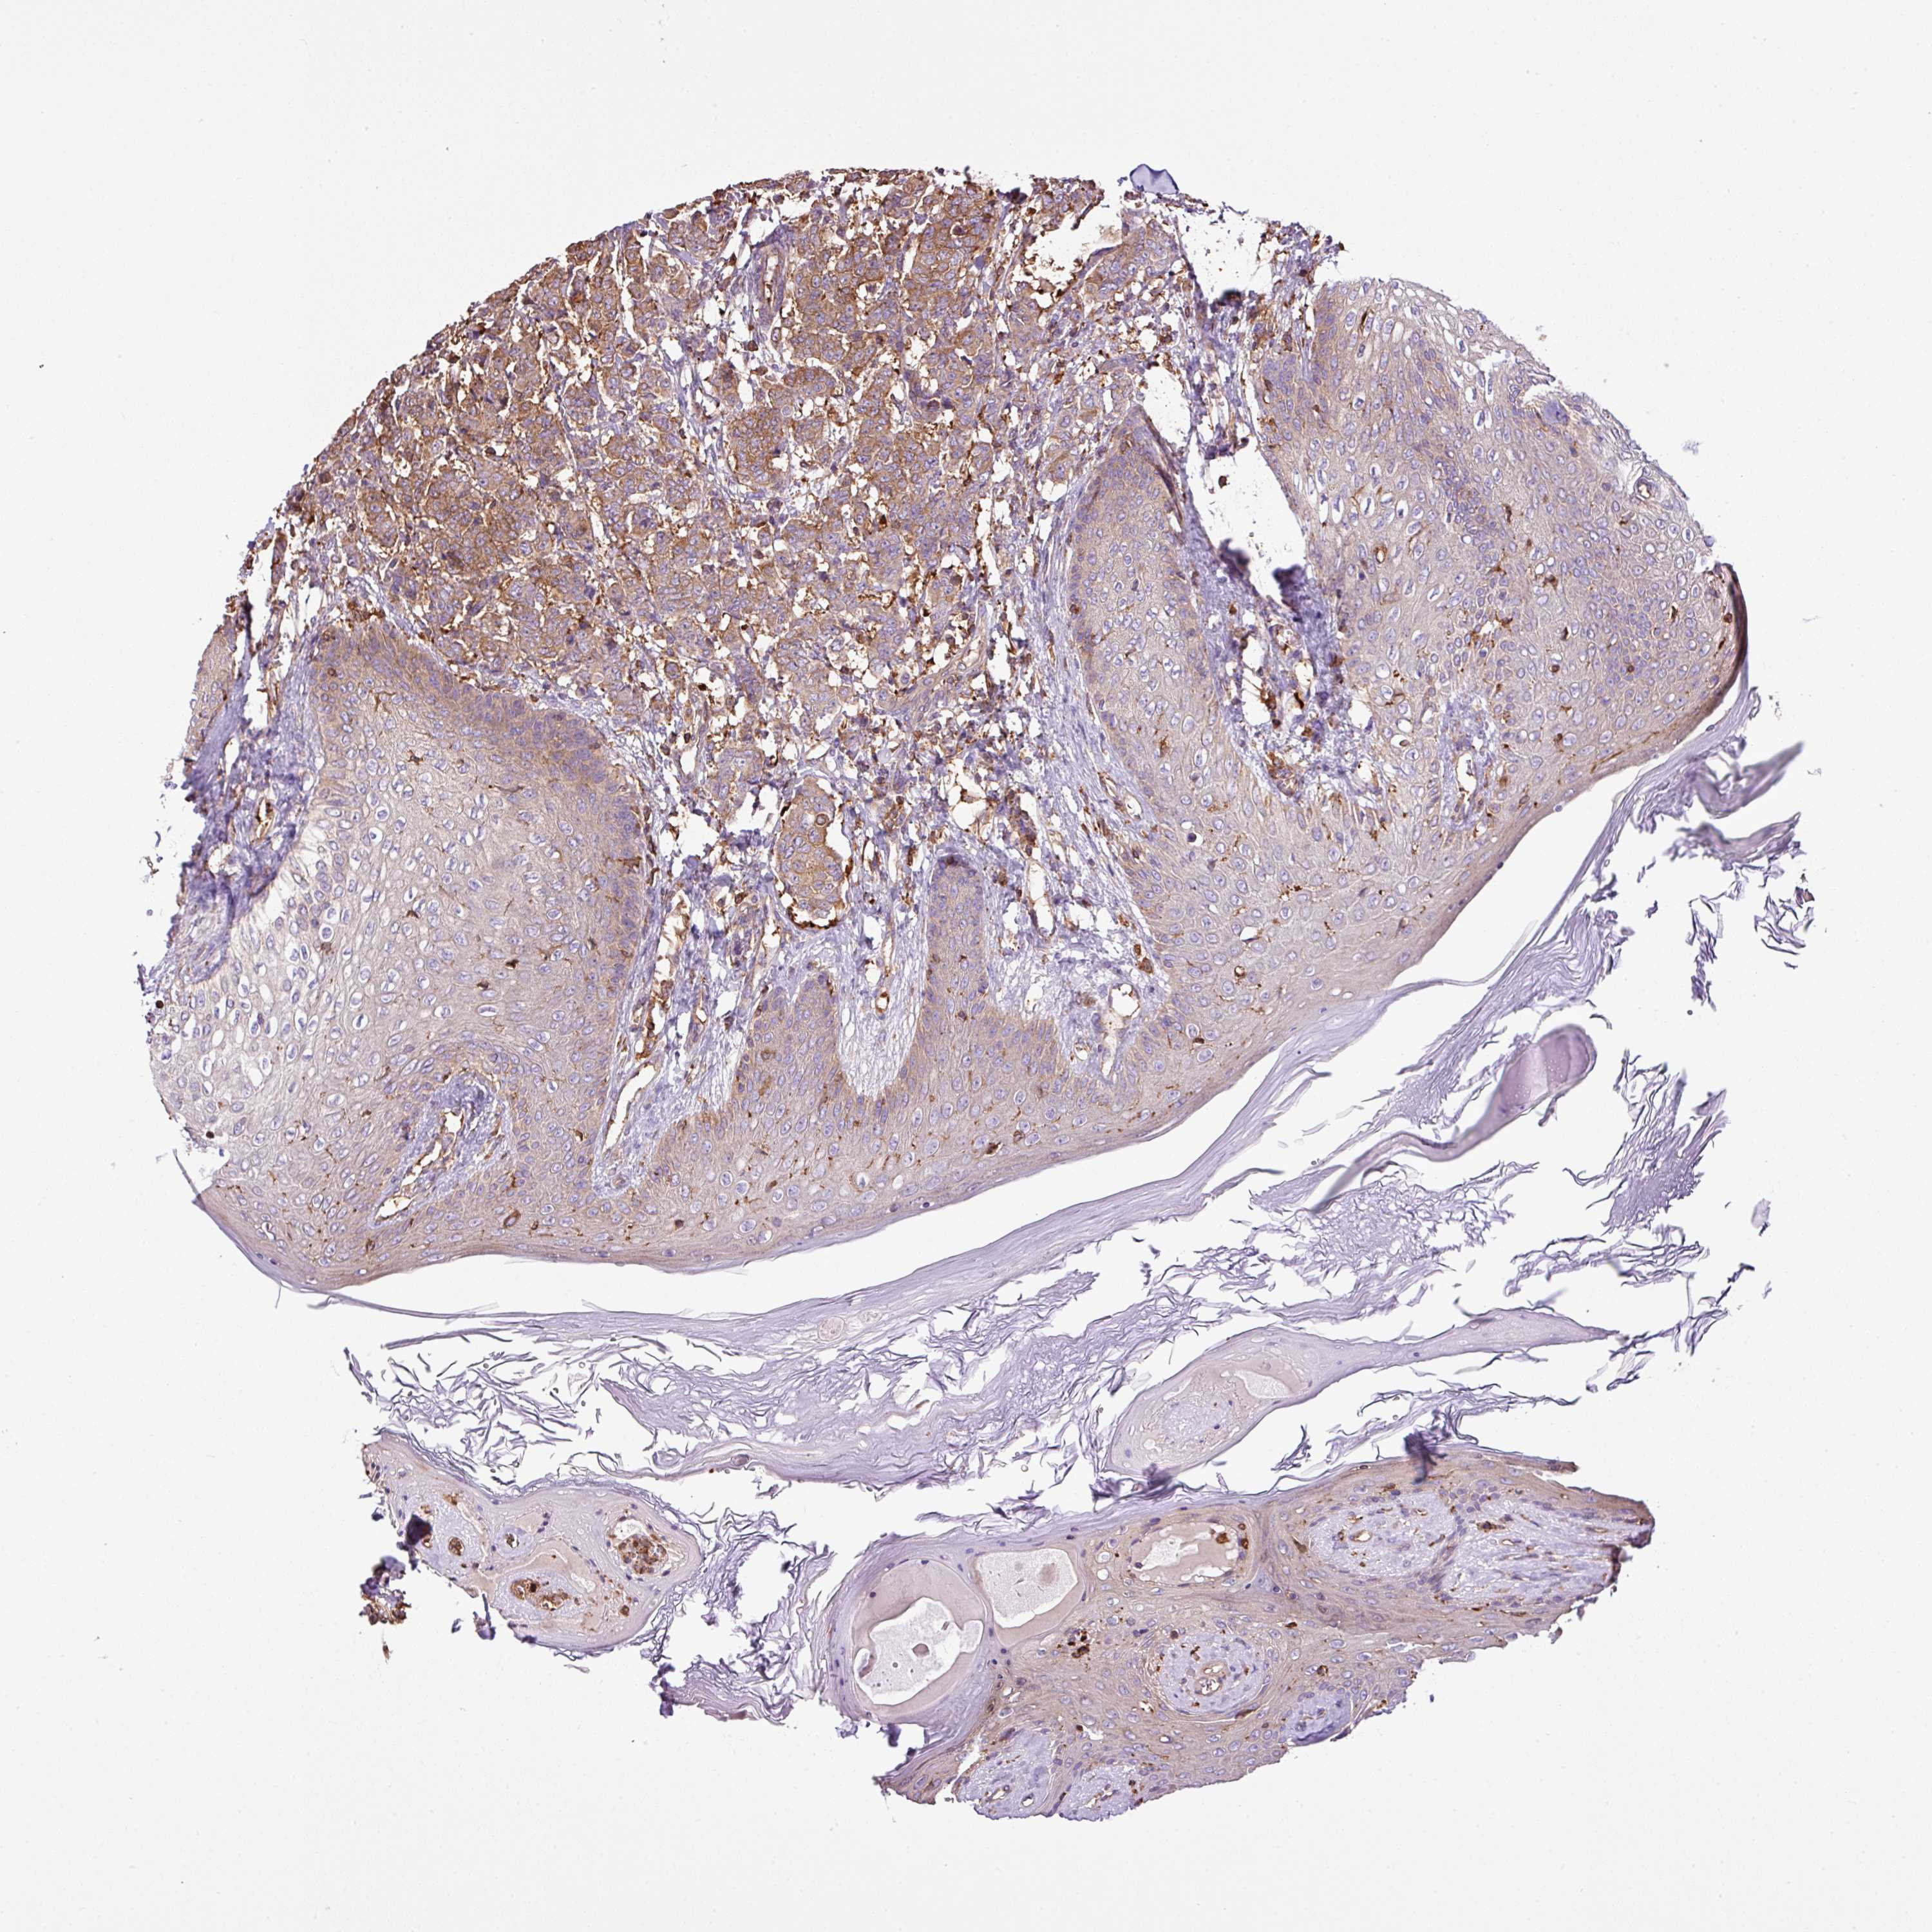

CANCER BREAST CANCER Show tissue menu

BRCA TCGA BRCA VALIDATION PROTEIN EXPRESSION